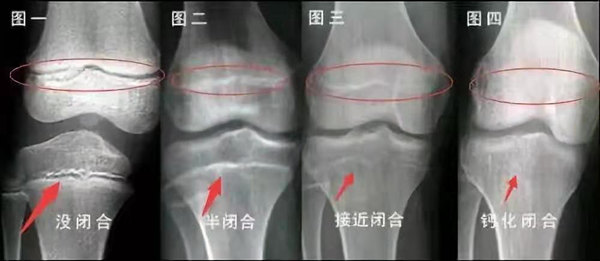

我們都知道,人體的高矮是由骨骼的生長發育決定的,特別是下肢長骨。長骨呈長管狀,在長骨的兩端有一種專管骨骼生長的骺軟骨,它與干骺端之間有一盤狀軟骨結構稱為骺板(線),在幼兒的X光片上表現為一條較寬的透光帶。 (見下圖)

未成年時隨著年齡的增加骺軟骨端不斷骨化,骨骼就不斷增長。當骨骺線完全閉合時骨骼就停止生長,個子也就不再增長了。一般骨骺端完全閉合的年齡是18~20歲左右。

一般來說,女孩的骨齡超過14歲,男孩的骨齡超過16歲,這時其骨骺線已接近閉合,基本沒有長高的機會了。

因此,越早了解骨骺線閉合情況,越早干預,孩子長高的可能性越大。